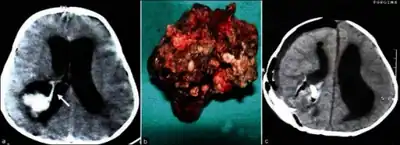

Choroid plexus papilloma, also known as papilloma of the choroid plexus, is a rare benign neuroepithelial intraventricular WHO grade I lesion found in the choroid plexus.[1] It leads to increased cerebrospinal fluid production, thus causing increased intracranial pressure and hydrocephalus.[2]

Choroid plexus papilloma occurs in the lateral ventricles of children and in the fourth ventricle of adults. This is unlike most other pediatric tumors and adult tumors, in which the locations of the tumors is reversed. In children, brain tumors are usually found in the infratentorial region and in adults, brain tumors are usually found in the supratentorial space. The relationship is reversed for choroid plexus papillomas.

Diagnosis

In terms of the diagnosis for Choroid plexus papilloma we find the following:[3]

- MRI

- Neuropathology (tumor tissue)

Treatment

Choroid plexus papillomas are benign tumors that are usually cured by surgery; malignant progression has been rarely reported.